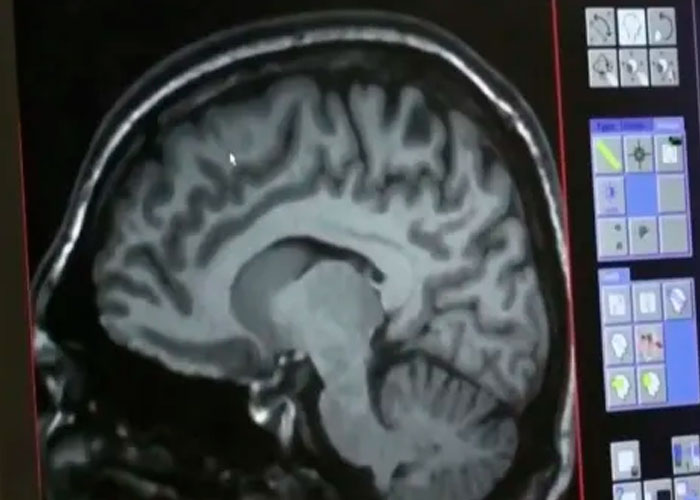

Una misteriosa enfermedad neurológica está afectando cada vez más a los habitantes de la provincia de New Brunswick, en Canadá según las declaraciones de un informante anónimo del sistema de salud de la provincia.

La rara e inexplicable condición, que se concentra en esta región de la costa atlántica de Canadá, ha sido analizada por investigadores durante más de dos años. Sin embargo todavía no se sabe qué es lo que la causa.

Inicialmente se creía que se trataba de una enfermedad priónica humana, en la que las proteínas llamadas priones provocaban que las proteínas normales se doblaran de forma anormal, pero las pruebas han descartado esa hipótesis